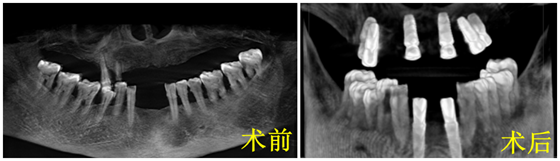

口腔外科主任伍栋副主任医师带领团队,对余阿姨制订了详细的诊疗方案。患者目前上半口牙缺失,下颌前牙区缺失,同时存在上颌后牙区牙槽骨严重吸收,种植难度大,需要精准植入种植体,经过设计共需要植入8枚种植体才能修复其口内所有缺失的牙齿,同时患者因术中无法沟通,为避免误吸、误吞等情况的发生,种植需在全麻下进行。

向峰主治医师在术前充分分析、反复论证、充分准备,重点评估患者的颌骨情况及全身情况。根据以往的种植经验,术中采取化繁为简的策略,上颌后牙区通过适当的倾斜植入植体,避免上颌窦提升植骨手术,这样不仅缩短了手术时间,而且减少了手术创伤,手术一气呵成。在麻醉手术部的保驾护航下,短短1小时内完成了8枚种植体植入,成功实施了种牙手术。术后患者复查口腔CT(锥体束CBCT),所有植体均精准植入,初期稳定性良好,术后三个月即可修复镶牙,目前余阿姨已顺利康复出院。